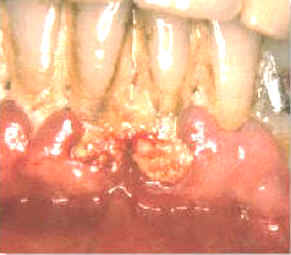

La imagen muestra como quedan las lesiones después de 14 días del tratamiento. El paciente ha realizado enjuagatorios de un minuto de duración  con 10 ml de chlorhexidine al 0.2% dos veces al día.

Además  ha mejorado su habilidad para cepillar sus dientes. Los dientes están relativamente  libres del placa dental pero se han  manchando por el clohexidine en las áreas proximales. Los tejidos blandos se encuentran sanos y aumentaron su firmeza, (resistencia al sondaje) y hay muy pocas zonas que sangran al sondaje.

El caso ilustrado demuestra la capacidad del tejido gingival de sanar cuando se elimina la placa, cemento y dentina infectados y cálculos. La curación es muy rápida si el paciente coopera con una buena higiene dental. En este caso particular el cambio es dramático.